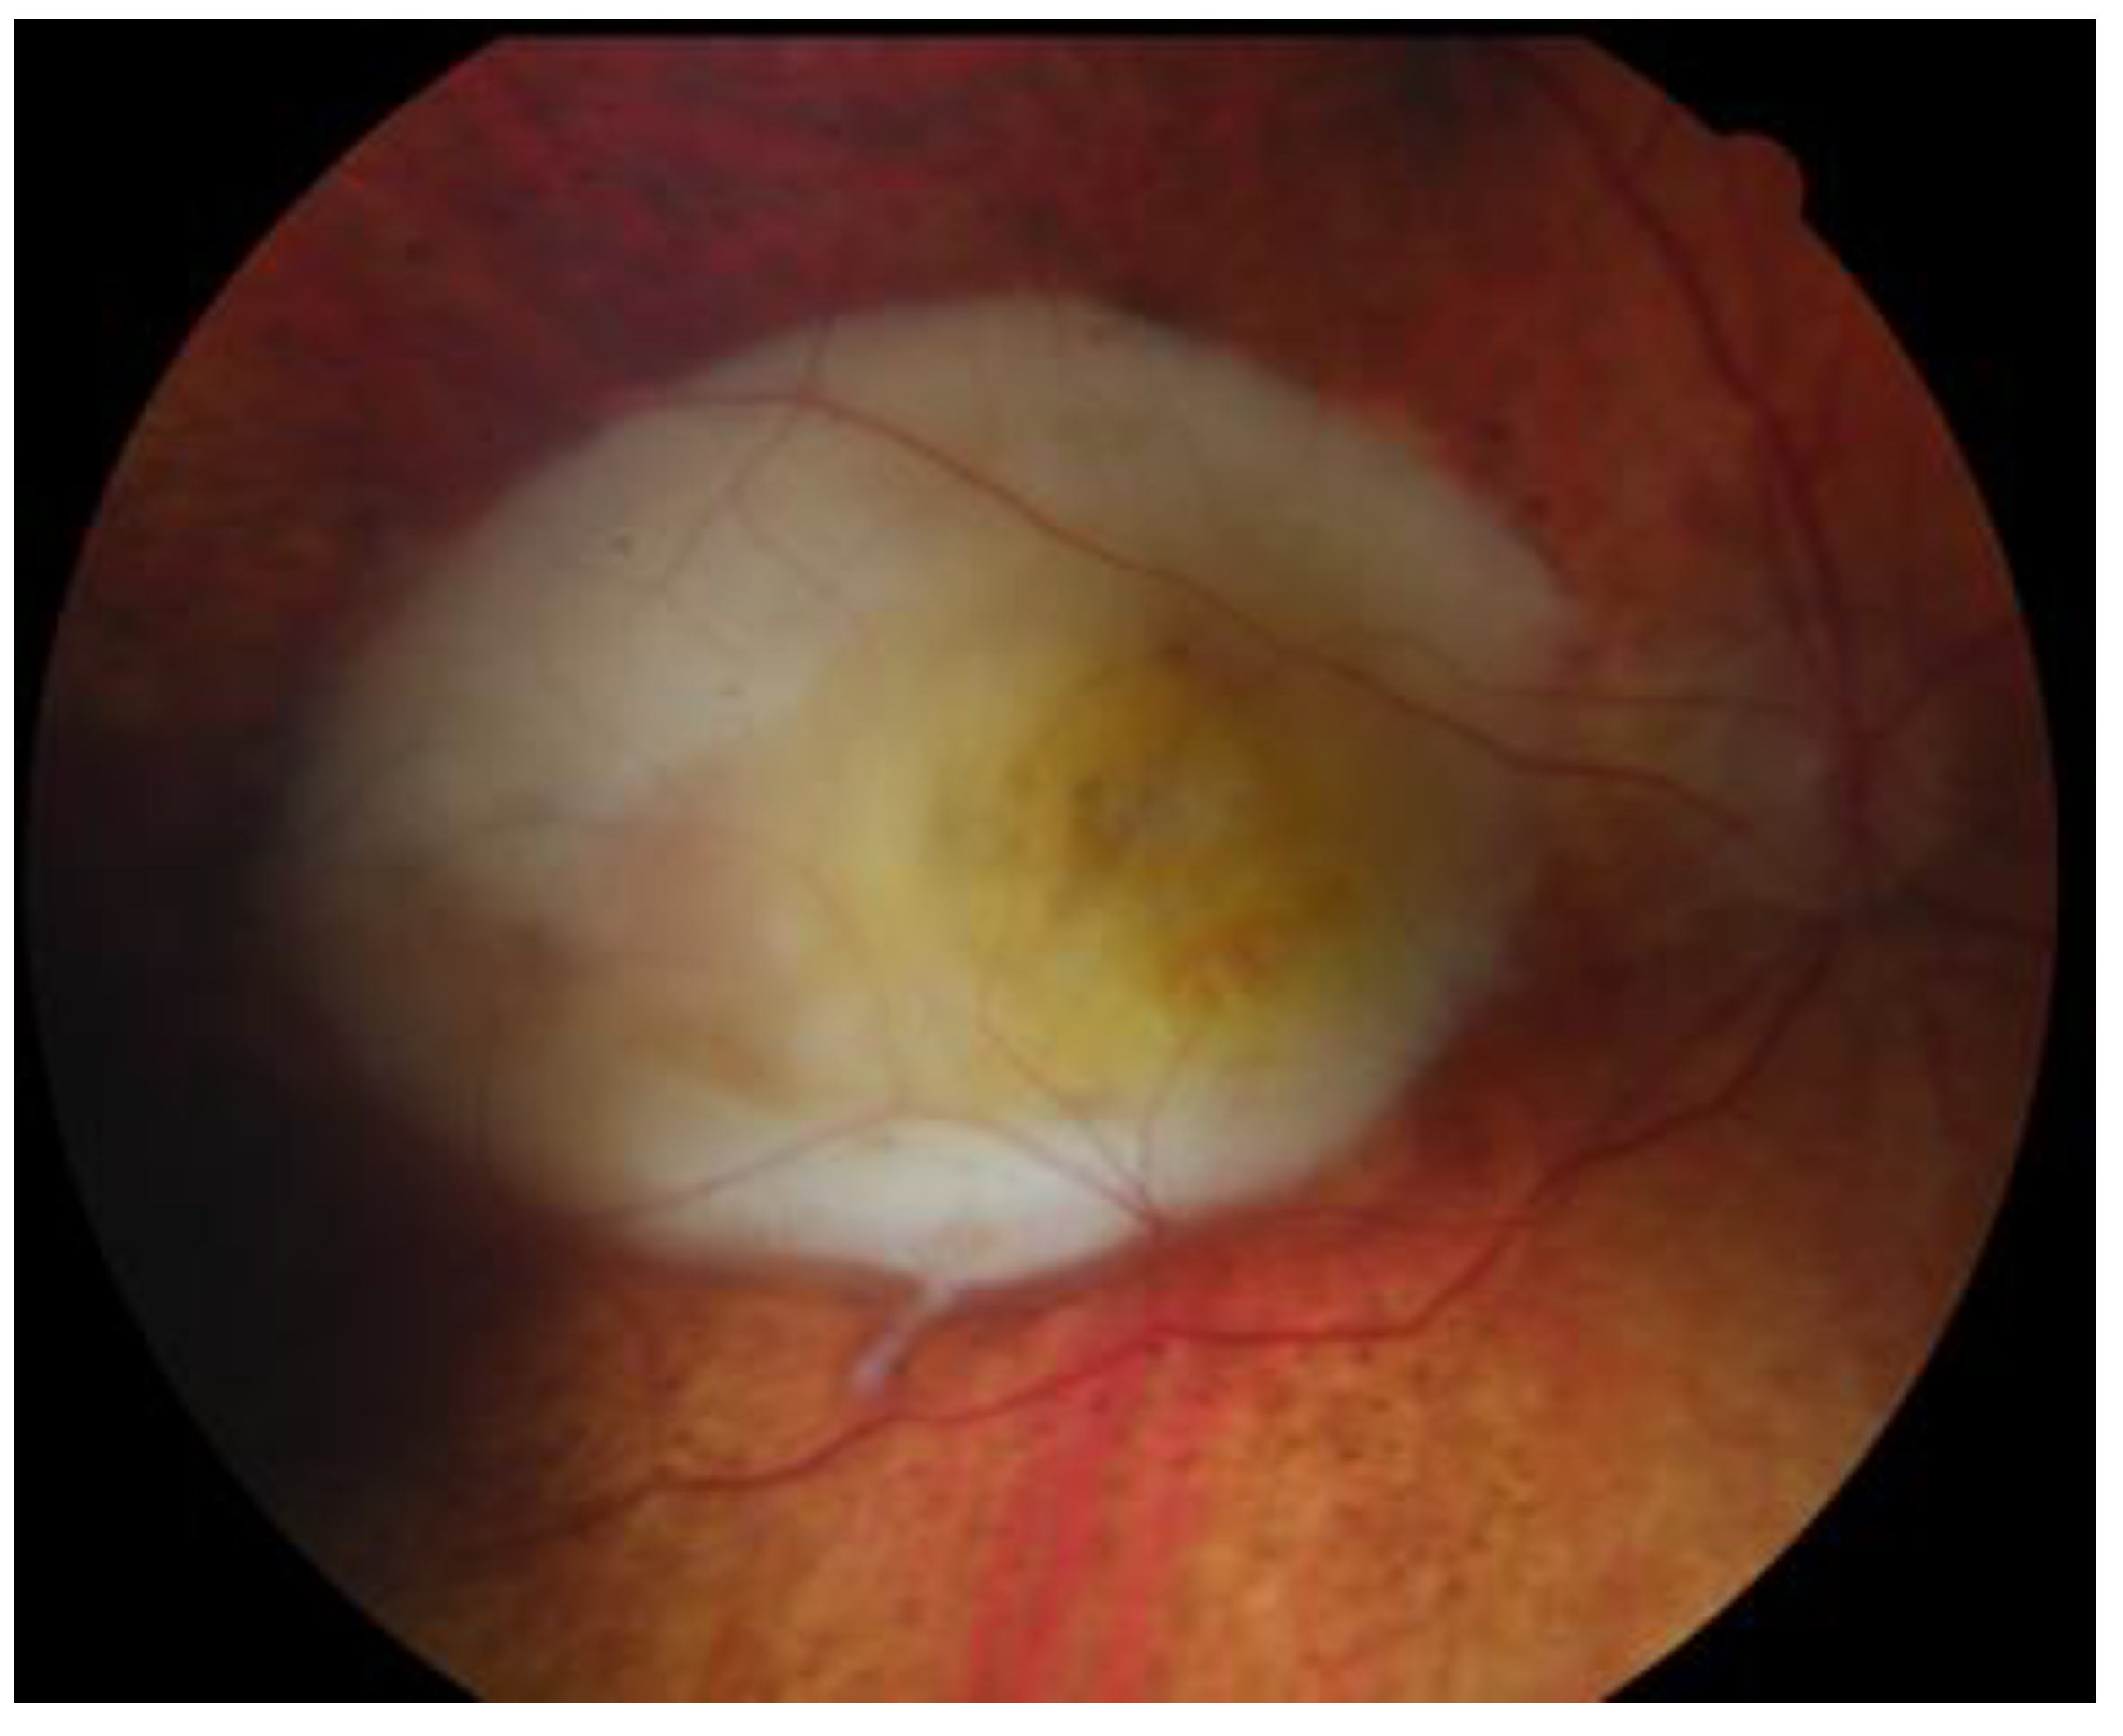

6. History

7. Physical Examination and Evaluation

8. Differential Diagnoses